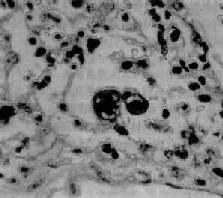

图9-21 腺病毒肺炎 图中央可见肿大肺泡上皮细胞中的核内包含体 有些混合感染,如麻疹病毒合并腺病毒感染,特别是又继发细菌感染的病毒性肺炎,病变更为严重,肺炎病灶可呈小叶性、节段性或大叶性分布。支气管和肺组织明显坏死、出血,并可混杂化脓性病变,从而掩盖了病毒性肺炎原来的病变特征。 (三)支原体肺炎 支原体肺炎(mycoplasmal pneumonia)是由肺炎支原体(mycoplasma pneumoniae)引起的一种间质性肺炎。支原体系介于细菌和病毒之间的微生物,共有30余种,其中多种可寄生于人体,但不致病,仅有肺炎支原体能引起呼吸道疾病。各种肺炎中约有5%~10%乃由肺炎支原体引起。主要经飞沫感染,秋、冬季节发病较多,儿童和青年发病率较高,通常为散发性,偶尔流行。患者起病较急,多有发热、头痛、咽痛及剧烈咳嗽(常为干性呛咳)等症状。胸部检查,可闻干、湿啰音。X线检查,肺部呈段性分布的纹理增加及网织状阴影。白细胞计数有轻度升高,淋巴细胞和单核细胞增多,痰、鼻分泌物及咽喉拭子能培养出肺炎支原体。 【病理变化】 肺炎支原体感染可引起整个呼吸道的炎症。肺部病变常仅累及一个肺叶,以下叶多见。病变主要发生于肺间质,病灶呈段性分布,暗红色,切面可有少量红色泡沫状液体溢出。气管或支气管腔内也可见粘液性渗出物。胸膜光滑。镜下,病变区域肺泡间隔明显增宽,有大量淋巴细胞、浆细胞和单核细胞浸润,肺泡腔内无渗出物或仅有少量混有单核细胞的浆液性渗出液。小支气管和细支气管壁及其周围组织也常有炎性细胞浸润。重症病例,上皮亦可坏死脱落,往往伴有中性粒细胞浸润。支原体肺炎预后良好。死亡率在0.1%~1%之间。

图9-19 支气管肺炎 图中见灶状实变的肺组织,肺泡内充满以中性粒细胞为主的炎性渗出物;病灶中有发炎的细支气管 【并发症】 小叶性肺炎发生并发症的危险性比大叶性肺炎大得多。可并发心力衰竭、呼吸衰竭、脓毒败血症、肺脓肿及脓胸等。支气管破坏较重且病程较长者,可导致支气管扩张。 【临床病理联系】 因小叶性肺炎多为其他疾病的并发症,其临床症状常为原发性疾病所掩盖。由于支气管粘膜的炎症刺激而引起咳嗽,痰呈粘液脓性。因病变常呈灶性散布,肺实变体征一般不明显。病变区细支管和肺泡内含有渗出物,听诊可闻湿啰音。X线检查,可见肺野内散在不规则小片状或斑点状模糊阴影。本病发现及时,治疗得当,肺内渗出物可完全吸收而痊愈。但在幼儿,年老体弱者,特别是并发于其他严重疾病时,预后大多不良。 (二)病毒性肺炎 病毒性肺炎(viral pneumonia)常常是因上呼吸道病毒感染向下蔓延所致。患者多为儿童,症状轻、重不等,但婴幼儿和老年患者病情较重。一般多为散发,偶可酿成流行。引起肺炎的病毒种类较多,常见的是流感病毒、还有呼吸道合胞病毒、腺病毒、副流感病毒、麻疹病毒、巨细胞病毒等等,也可由一种以上病毒混合感染并可继发细菌感染。病毒性肺炎的病情、病变类型及其严重程度常有很大差别。 【病理变化】 早期或轻型病毒性肺炎表现为间质性肺炎,炎症从支气管、细支气管开始,沿肺间质发展,支气管、细支气管壁及其周围、小叶间隔以及肺泡壁等肺间质充血、水肿,有一些淋巴细胞和单核细胞浸润,肺泡壁明显增宽(图9-20)。肺泡腔内一般无渗出物或仅有少量浆液。病变较重者,肺泡也可受累,出现由浆液、少量纤维蛋白、红细胞及巨噬细胞组成的炎性渗出物,甚至可发生组织坏死。有些病毒性肺炎(如流感病毒肺炎,麻疹病毒肺炎、腺病毒肺炎等)肺泡腔内渗出较明显,渗出物浓缩凝结成一层红染的膜样物贴附于肺泡内表面,即透明膜形成。支气管上皮的肺泡上皮也可增生,甚至形成多核巨细胞。麻疹病毒肺炎的病变特点为在间质性肺炎的基础上,肺泡壁上有透明膜形成,并有较多的多核巨细胞(巨细胞肺炎),在增生的上皮细胞和多核巨细胞的胞浆内和胞核内可检见病毒包含体。病毒包含体常呈球形,约红细胞大小,呈嗜酸性染色,均质或细颗粒状,其周围常有一清晰的透明晕。其他一些病毒性肺炎也可在增生的支气管上皮、支气管粘液腺上皮或肺泡上皮细胞内检见病毒包含体。如腺病毒肺炎可在增生的上皮细胞核内(图9-21),呼吸道合胞病毒肺炎可在增生的上皮细胞胞浆内,巨细胞病毒肺炎也可在增生的上皮细胞核内检见病毒包含体。检见包含体是病理组织学诊断病毒性肺炎的重要依据。